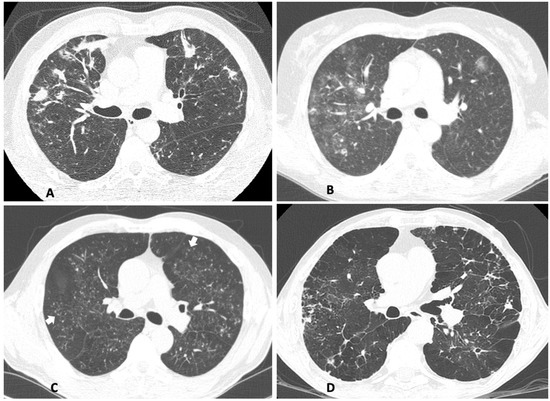

| HRCT Features | Female (n = 13) | Male (n = 21) |

|---|---|---|

| Nodules | 10 77% | 15 71% |

| Ground-Glass Opacities | 12 * 92% | 11 * 52% |

| Micronodules | 9 69% | 13 62% |

| Paraseptal/Centrolobular Emphysema | 4 * 31% | 14 * 67% |

| Bronchial Wall Thickening | 7 54% | 11 52% |

| Parenchymal Bands | 4 31% | 12 57% |

| Interlobular Septal Thickening and/or Reticulation | 6 46% | 8 38% |

| Mediastinal Lymphadenopathy | 4 31% | 10 48% |

| Paracicatricial Emphysema | 2 15% | 9 43% |

| Cavities | 4 31% | 6 29% |

| Architectural Distortion | 1 8% | 5 24% |

| Consolidation | 3 23% | 3 14% |

| Pleural Effusion | 1 8% | 2 10% |

| Pleural Thickening | 0 0% | 2 10% |